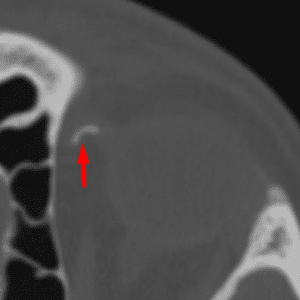

Medial Occipital Condyle "Notch"

Medial Occipital Condyle “Notch”

Mimicking fracture